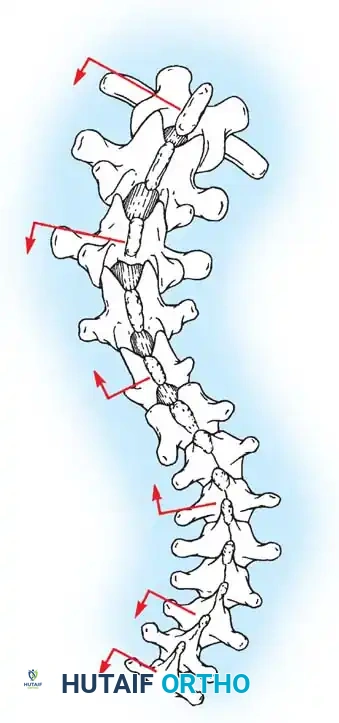

Biomechanics of Bone Grafting

Bone graft incorporates most effectively under compressive loads and is biologically disadvantaged in environments of distraction. Therefore, in scoliosis correction, if autogenous bone is limited, it should be preferentially concentrated on the concave side of the curve, which is subjected to compressive forces, rather than the convex side, which experiences tension. Furthermore, the farther the fusion mass is placed from the instantaneous axis of rotation, the more effectively it will neutralize movement across that axis.